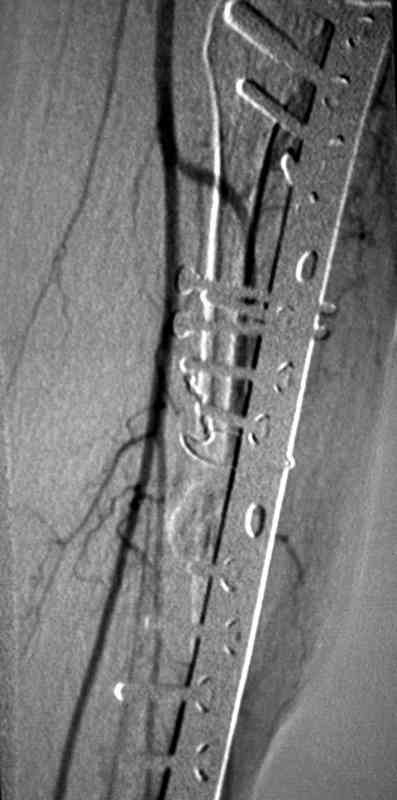

инфицированный с металлоконструкцией ложный сустав

ангиография,